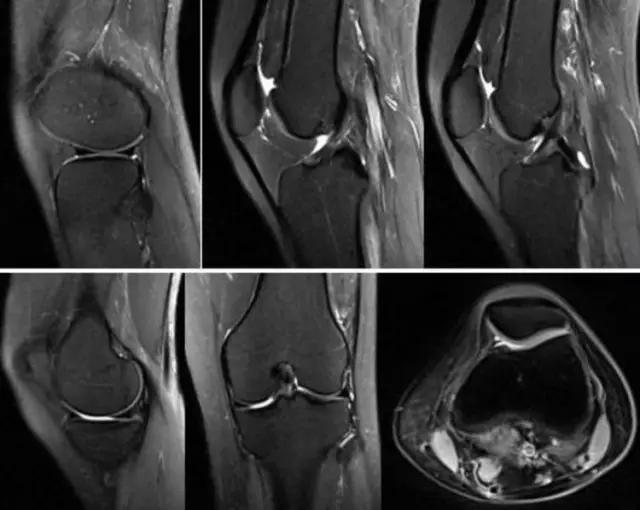

我们可能都不熟悉T1、T2,怎么办?当我们发现有问题后,利用照片上图像的对比,推测病变的可能也是一种诊断方法。病例:黄XX,女,39岁,左膝关节反复交锁1年。图1:肿物信号与骨信号一样图2:肿物信号与骨信号一样图3:肿物信号与骨信号不一样 肿物应该与骨相关,但不是骨性,推断:膝关节滑膜软骨瘤。手术后得到证实。